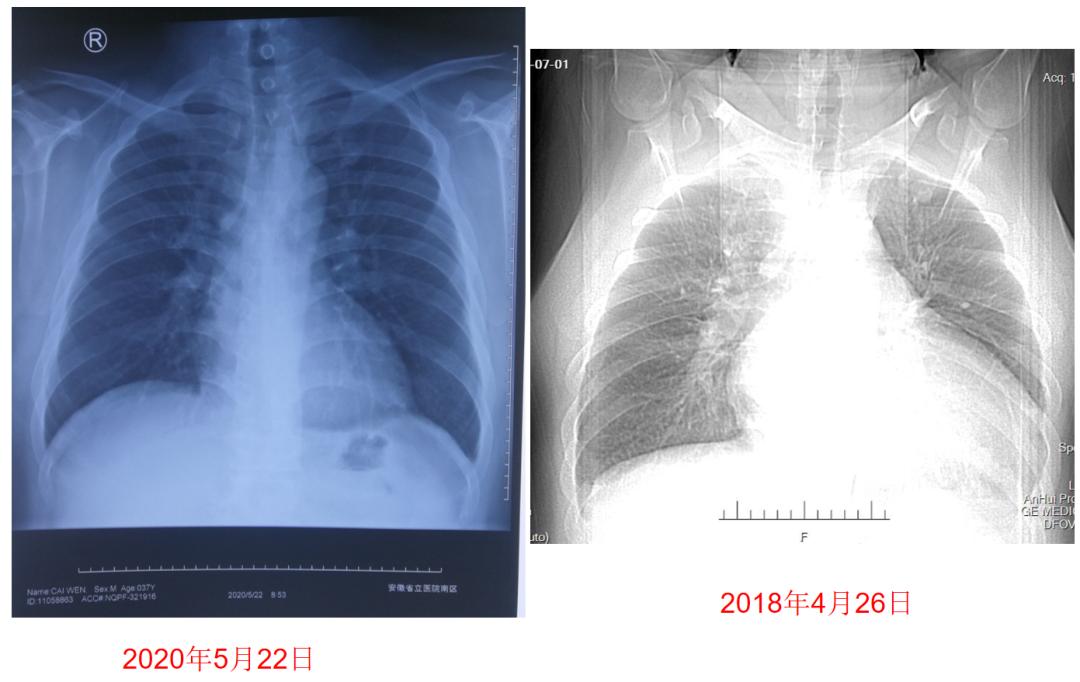

▎ 胸片:心影增大、肺部感染。

图2:患者入院胸片

图5:患者药物治疗前后胸片检查对比